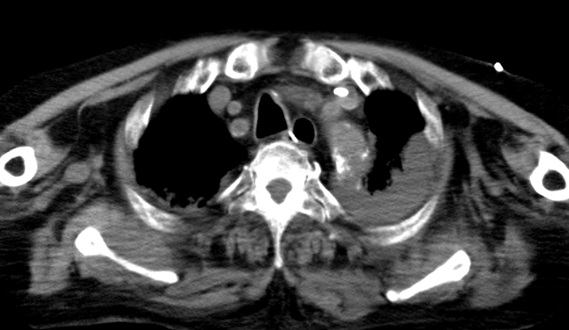

- 9月12日:血胸(緊張性血胸)の痕跡

胸部CTでフィブリン化、血餅化した胸水の遺残や大動脈周囲の血種の所見が認められる。 心嚢水貯留のみでは輸血が必要になるほどの貧血は起こり得ず、より広いスペースへの出血が起こっていたと考えられる。 そのスペースは胸腔や縦郭と考えられ、その原因は当初行われたPCI(経皮的冠動脈形成術)での血管損傷であったと考えられる。

証拠:胸腹部CT・血胸・大動脈周囲の血種像

この時、同時に撮影された胸腹部CTでは、大動脈周囲に三日月状の血種様の病変が認められ、両胸腔にはフィブリン化したと思われる血餅の残存病変が多数認められた。血管損傷に伴い胸腔に出血していた証拠であり、当初のPCI(カテーテル治療)での大事故の痕跡がこのCT画像に残っている。